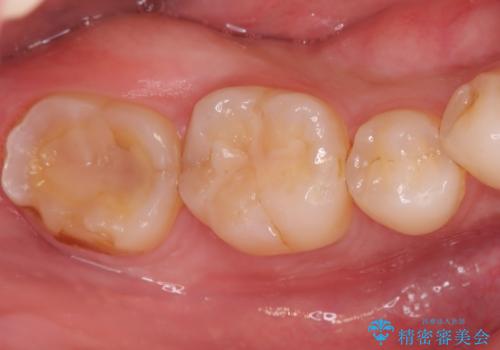

セラミッククラウンによる奥歯の修復

担当医 河口智英